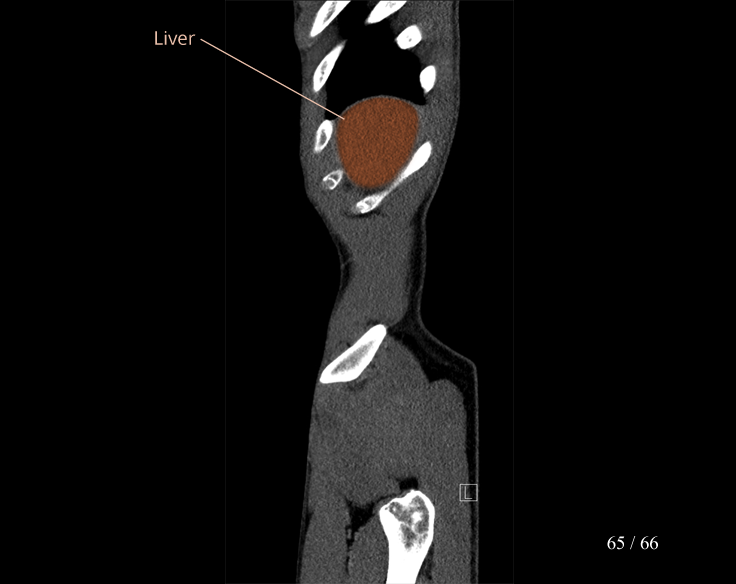

Body

Covers abdominal CT anatomy.